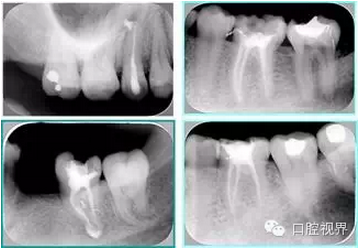

共有 4 張 X 線片,分別是術(shù)前、診斷絲 、主牙膠尖確認(rèn)、術(shù)后。

( 1 )術(shù)前:術(shù)前 X 線片用來了解牙齒的大概情況。術(shù)前預(yù)期為多根牙時(shí) X 線片應(yīng)偏頭拍攝。

( 2 )診斷絲:根據(jù)術(shù)前 X 線片進(jìn)行開髓、根管的初步預(yù)備后,需要插入診斷絲,用來指示工作器械位置。常用 10 號(hào)或 15 號(hào)擴(kuò)大器作為診斷絲插入牙髓腔。

( 3 )主牙膠尖確認(rèn):通過術(shù)前預(yù)期和診斷絲診斷,明確工作長度、牙根走向,進(jìn)行根管預(yù)備。之后應(yīng)進(jìn)行主牙膠尖(中銼)確認(rèn),已明確根管是否適合充填。

( 4 )術(shù)后:觀察治療效果。

左圖為根管充填術(shù)后 X 線片。圖中可見,根管充填較好。右下圖有白色小點(diǎn),為側(cè)方加壓導(dǎo)致糊劑擠出所致,表明根管充填比較致密。

致密、恰到好處的充填可去除干凈根管里感染灶,機(jī)體逐漸恢復(fù)。

多根牙時(shí)候需進(jìn)行偏移投照,正位投照無法說明具體哪根牙根管充填效果。